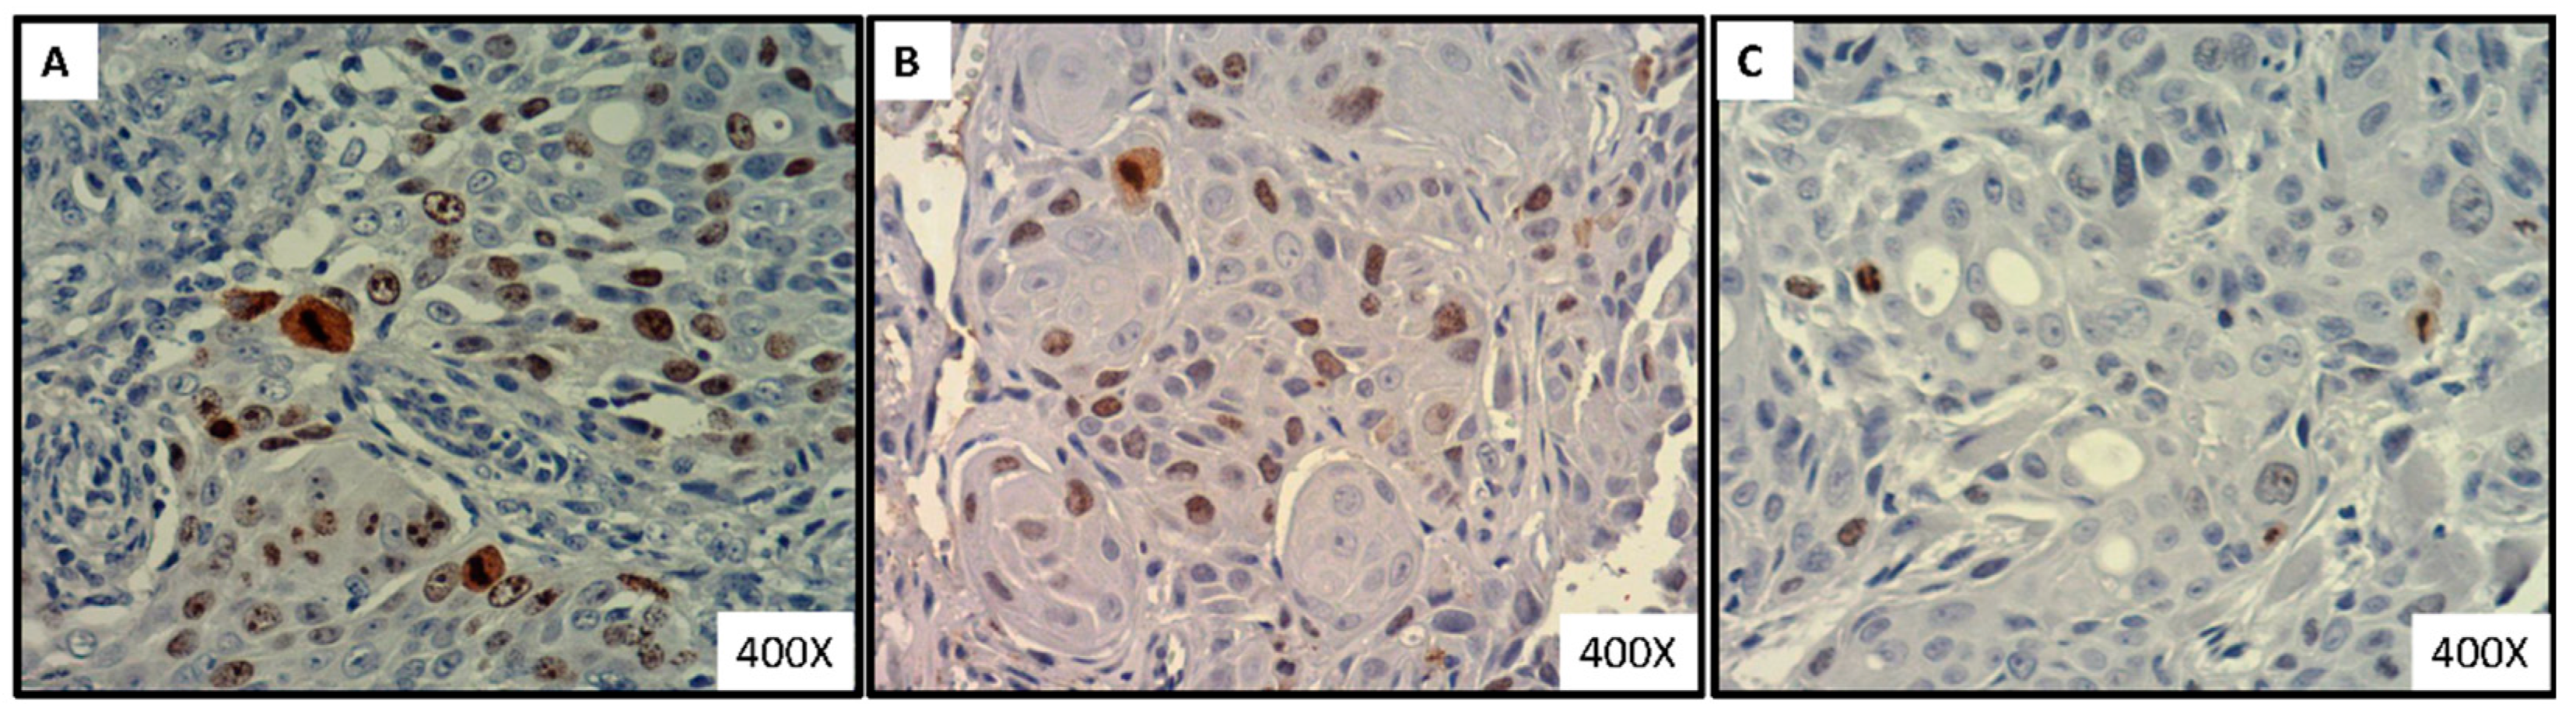

3.6. Significant Decrease in the Intense-to-Mild Staining Ratio of Proliferation Marker Ki-67 in Tongue Tumor of Xylitol-Treated Mice, Compared to Control Group